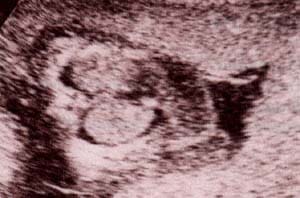

Diagnóstico Prenatal -  bolsa escrotal y su contenido Diagnóstico Prenatal -  30 semanas. se observan los testículos

fig. 51.– (a). bolsa escrotal y su contenido. 25 semanas. fig. 51.– (b). 30 semanas. se observan los testículos en un corte perpendicular al polo pélvico.